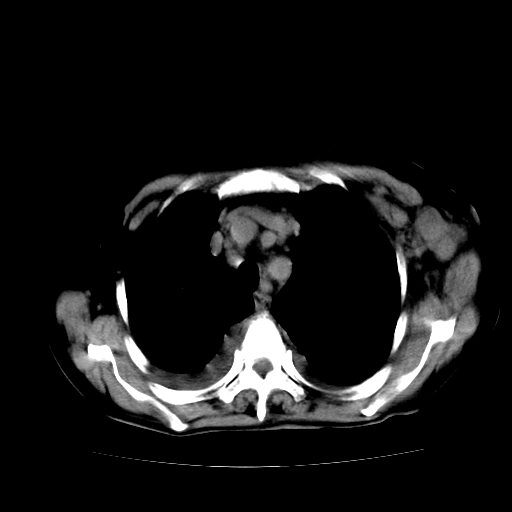

癌性淋巴管炎,肝脏转移,瓷胆囊

1)左侧乳腺癌并左侧腋窝及纵隔淋巴结转移,两肺淋巴道转移(癌性淋巴管炎),肝脏多发性转移。2)双侧胸腔积液。3)慢性胆囊炎。

5、肝转移瘤;

6、瓷胆囊。

1)左侧乳腺癌并左侧腋窝及纵隔淋巴结转移,肝脏多发性转移。2)双侧胸腔积液伴双肺蝶翼样磨玻璃高密度影,双侧肺门血管影增粗(图像不全,肺门层面没纵隔窗),考虑心功能不全所致。3)慢性胆囊炎伴壁钙化。